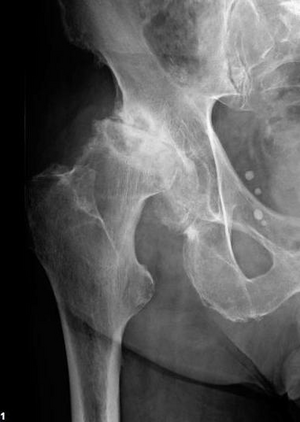

Häufigste Ursache für den Ersatz des Hüftgelenks ist der anlagebedingte Verschleiß des Knorpelüberzugs am Hüftgelenk, die Hüftgelenksarthrose. Diese verursacht zunehmende Schmerzen sowie eine verminderte Beweglichkeit und Belastbarkeit des Gelenks. Weitere Ursachen sind angeborene Fehlbildungen (z. B. Hüftdysplasie) sowie Folgeschäden nach Unfällen oder das Absterben des Hüftkopfes infolge einer Mangeldurchblutung (Hüftkopfnekrose). Des Weiteren steigt aufgrund der zunehmenden Lebenserwartung die Zahl der Oberschenkelhalsbrüche. Diese werden in der Regel ebenfalls mit dem Einbau einer Hüftendoprothese behandelt.